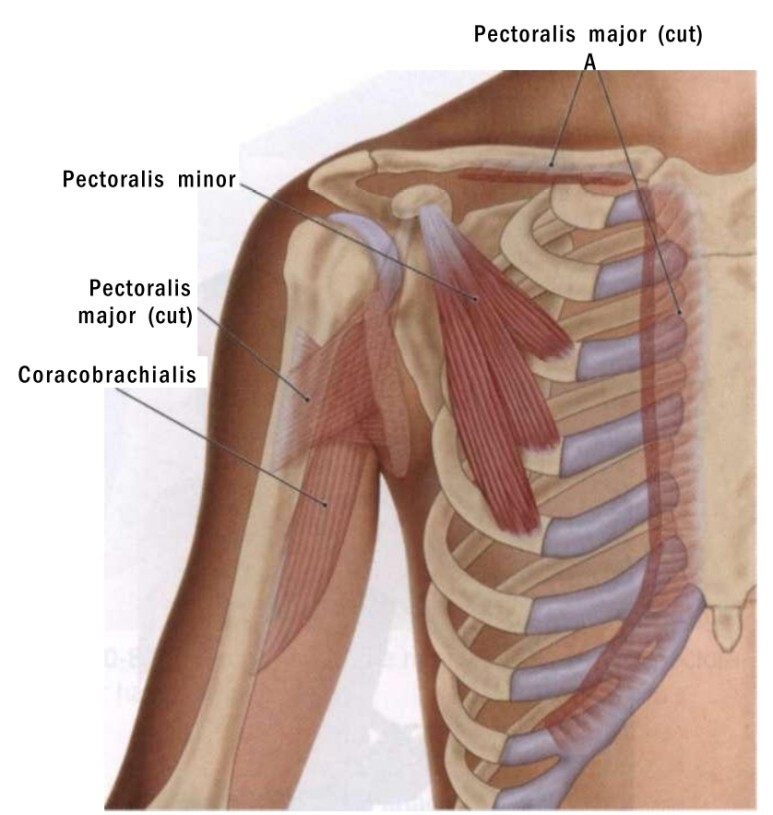

촉진 / Palpation

<시작 자세>

· 환자는 바로누운자세(supine)를 취하고 손을 등허리에 위치한다.

· 치료사는 환자의 옆에 앉는다.

· 촉진하려는 손을 환자의 어깨뼈부리돌기(coracoid process)의 바로 아래에 위치시킨다.

<촉진 단계>

· 환자에게 손과 전완으로 베드를 아래를 향하여 누르도록 지시하고, 대흉근/큰가슴근을 통하여 소흉근/작은가슴근의 수축을 느낀다.

· 계속해서 갈비뼈 부착부위까지 근섬유의 수직방향으로 촉진한다.

· 소흉근/작은가슴근 촉진을 완료시 환자에게 편안한 자세를 취하게하고 기본톤(baseline tone)을 평가하고 촉진한다.